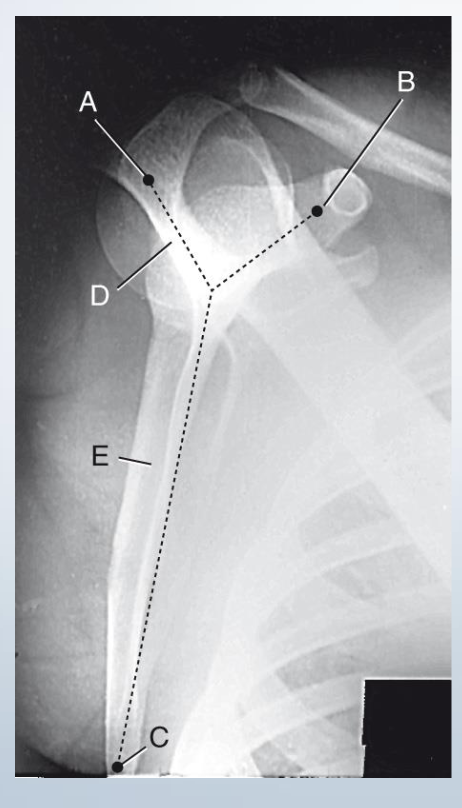

Spapular Y Lateral

A. Acromion

B. Coracoid Process (always closest to ribs)

C. Inferior Angle

D. Spine of scapula

E. Body of scapula